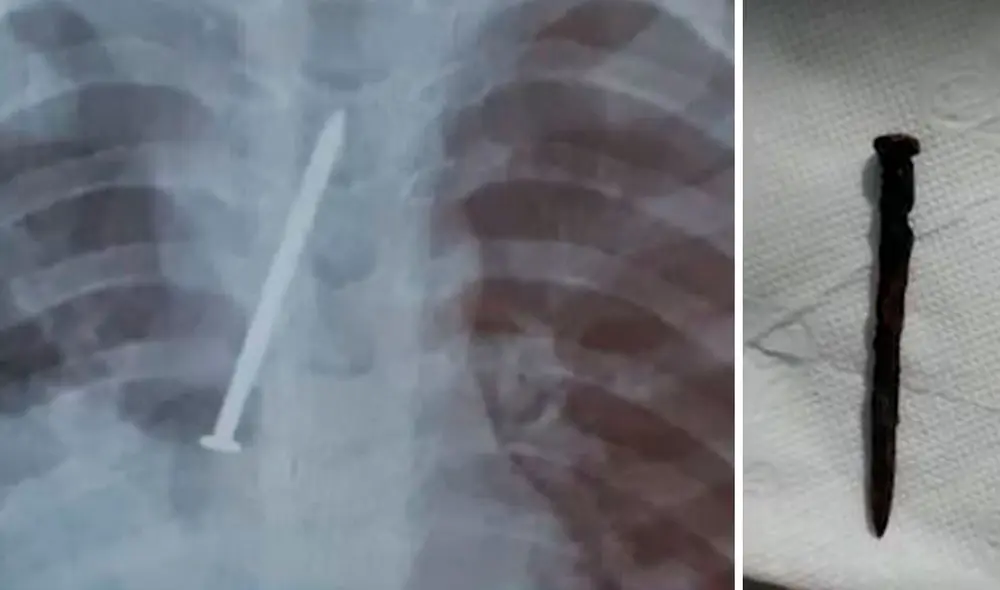

Brasil. Un niño de 3 años murió tras pasar un año con un clavo incrustado en sus pulmones, estado que se extendió tanto tiempo, denuncian los padres por negligencia de los doctores, quienes supuestamente solo se dedicaron a tratar los síntomas y no ordenaron exámenes.

El pequeño falleció tras un episodio de bronconeumonía debido a que tenía ambos pulmones perforados por el objeto extraño, según el informe médico. Por ello, los progenitores denunciaron que su hijo murió por negligencia médica en el Hospital Municipal de Canavieiras.

El profesional prescribió medicación, nebulizó y dio de alta al niño para que regresara a su casa. Al ver a su hijo realmente grave, Cosme y Clarice decidieron pagar un examen particular. Los rayos x confirmaron que había un objeto extraño en el cuerpo y que debía ser operado de urgencia.

En el Hospital General del Estado (HGE), el nene fue operado para quitarle el clavo de sus pulmones. Los galenos descubrieron que el material había perforado ambos pulmones del pequeño, quien estuvo días hospitalizado en la Unidad de Cuidados Intensivos (UCI) antes de fallecer.